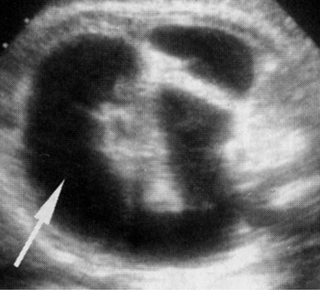

Υπερηχογραφικά, παρατηρείται χαρακτηριστικά το σημείο της διπλής φυσαλίδας,

που οφείλεται στο διατεταμένο στόμαχο και το εγγύς τμήμα του δωδεκαδακτύλου,

σε συνδυασμό με υδράμνιο (στο 17-53% των περιπτώσεων) (εικόνα 20). Παρόλο που

η χαρακτηριστική διπλή φυσαλίδα μπορεί να παρατηρηθεί από τις 20 εβδομάδες,

συνήθως δεν γίνεται εμφανής πριν τις 25 εβδομάδες της κύησης. Η επιβίωση μετά

| Εικόνα 20. Ατρησία 12δακτύλου. | Εικόνα 21. Ατρησία ειλεού. |